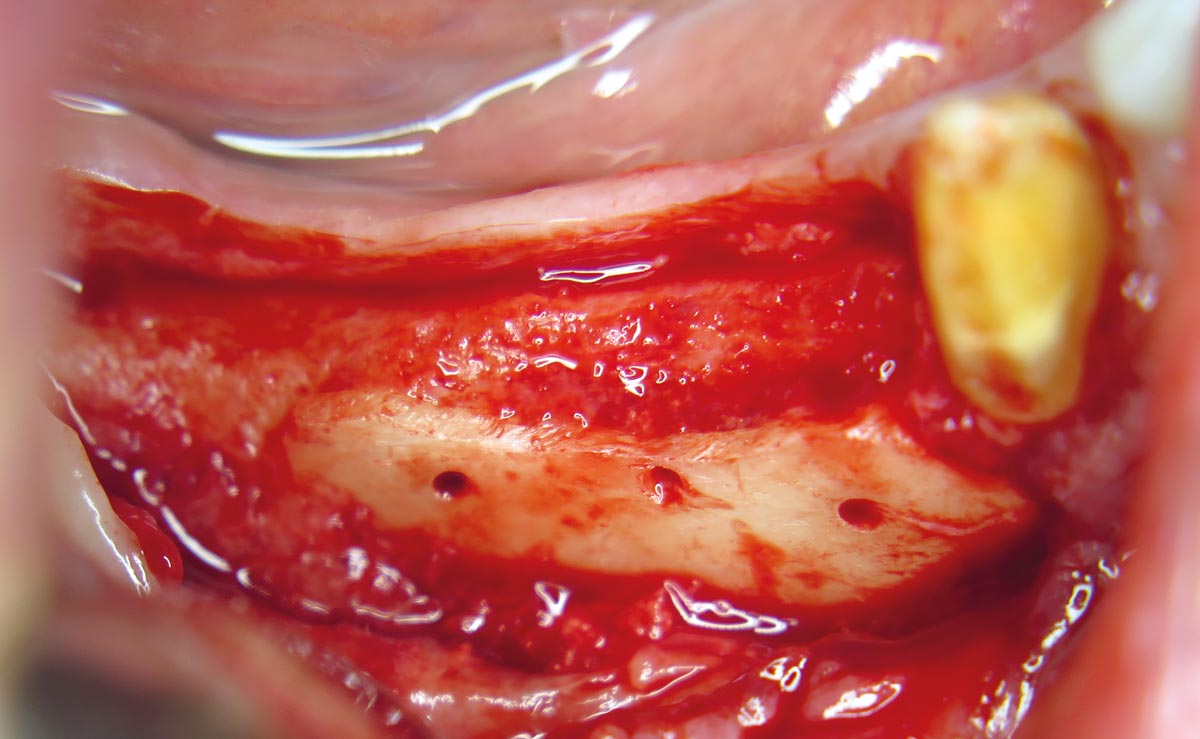

03 / 20 - Flap projection shows pronounced bone lossHorizontal ridge augmentation with maxgraft® cortico - M.Sc. E. Kapogianni

04 / 20 - Decortication of the host bone and fixation of a defect-adapted cortical plateHorizontal ridge augmentation with maxgraft® cortico - M.Sc. E. Kapogianni